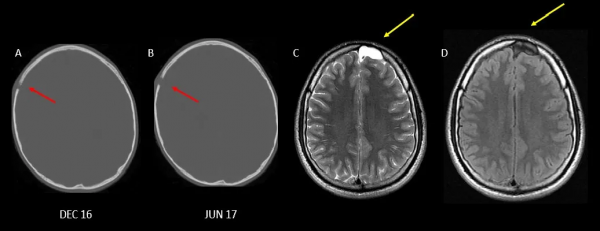

A:雙側頂骨孔;B:單側頂骨孔;C:單側枕骨孔;D:擴大的盲孔;E-F:縫間骨;蛛網膜顆粒壓跡

縫間骨

A-C:乳突導靜脈:透過乳突導靜脈將硬腦膜的靜脈竇與顱骨外部的靜脈連線起來;D:顱骨瀰漫性增厚;E:額竇過度氣化;F-G:枕骨過度氣化;H:顳骨過度氣化